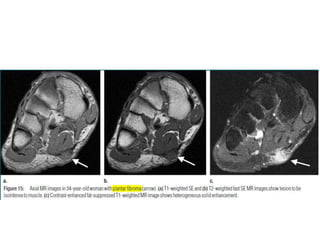

17-year-old girl with synovial sarcoma of foot

who presented with slowly growing painless

mass.